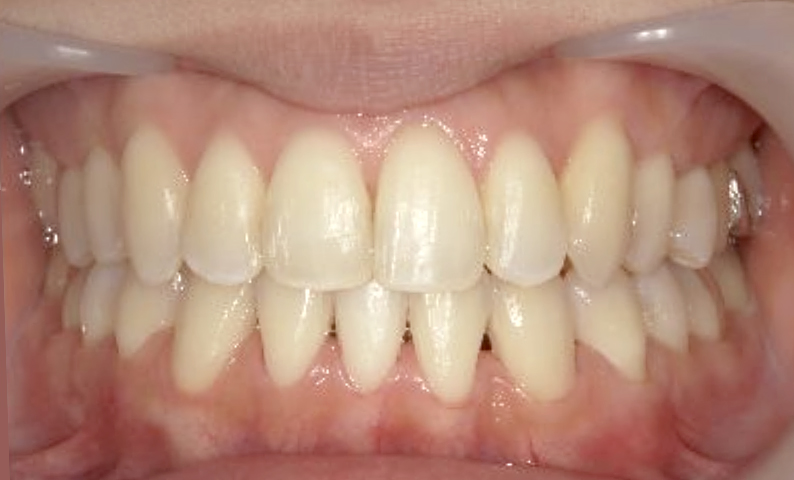

症例_019 上下顎の部分矯正

治療期間:8ヶ月金額:48万円+税女性前歯のガタガタ

| Before | After |

|---|---|

|